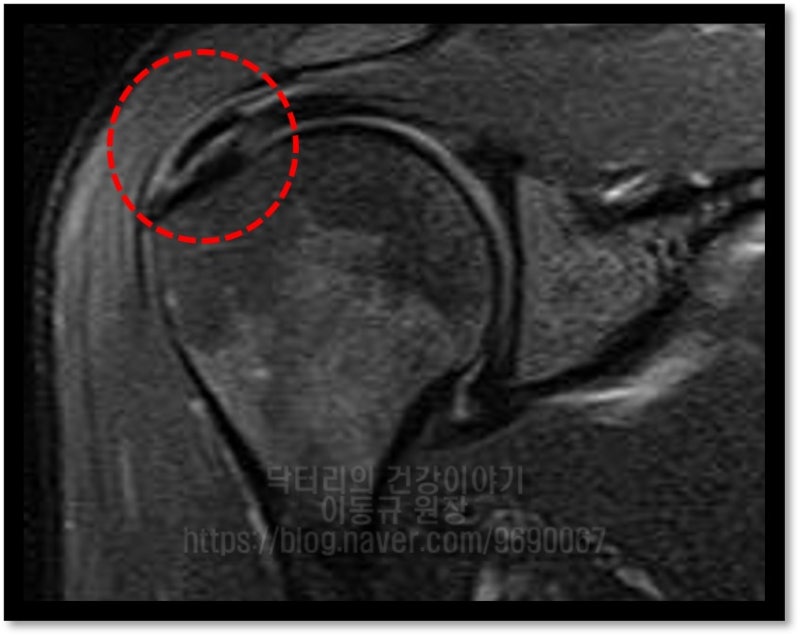

타병원에서 거의 1년 가까이 치료를 받았으나 석회의 크기가 줄어들지 않아 수술적 치료를 권고 받았으나 수술적 치료를 하기가 힘든 상황으로 비수술적 치료를 원하여 본원으로 오셨다고 합니다. 힘줄의 상태를 확인하기 위해 초음파 및 MRI 검사를 시행하였습니다.

좌측 MRI 사진에서 빨간 원안에 극상근 내부에 검게 보이는 것이 석회입니다. 우측 초음파 사진에서 빨간 점선으로 표시된 것이 극상근 내부에 있는 석회 입니다. 석회성 건염 이외에는 다른 소견은 없어 보입니다.